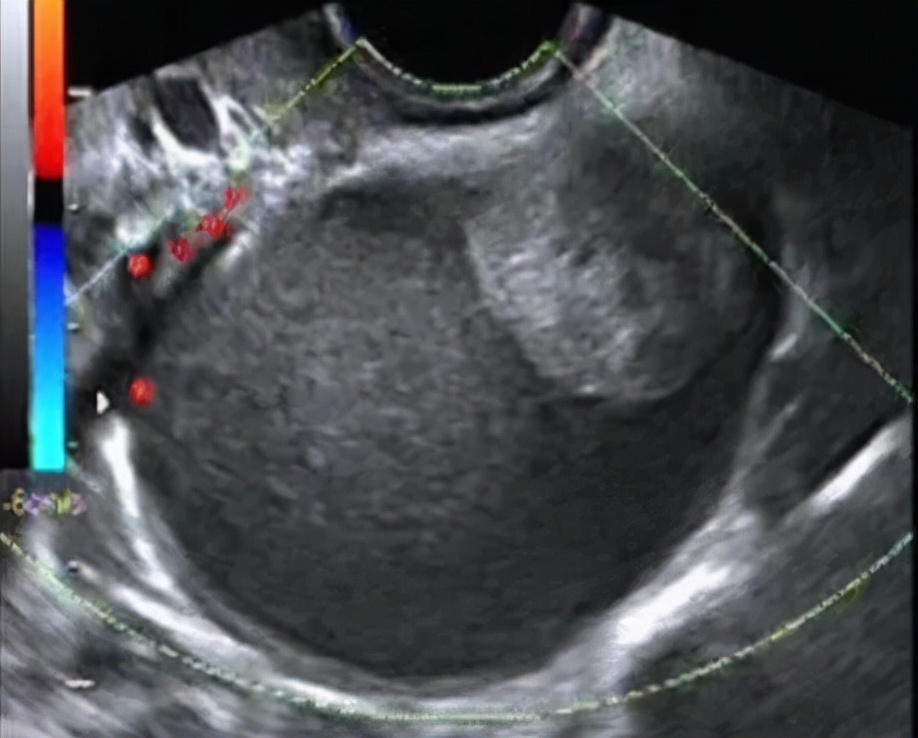

卵巢生理性囊肿特点: 囊壁菲薄,内壁光滑,透声好,直径基本<4-5cm。超声多普勒血流检测提示没有明显的血流信号。多数会消失,一般建议1-3个月后月经干净3天左右复查,因为这时新的一批卵泡尚未发育起来,所有没有二次干扰,可以判断它是否真的消失了。

卵巢子宫内膜异位囊肿特点: 囊肿可在双侧卵巢或单侧卵巢发病,因病程的长短及月经周期时相不同,表现不同,可伴有痛经、也有不痛经,体检的时候才被发现的,早期超声表现与黄体血肿类似,典型的成熟巧囊表现为囊肿内细密均匀的光点状回声。需要动态复查,酌情手术治疗及辅助治疗;个别巧囊经过长时间的演进,也有变成癌的,所以也要引起重视!